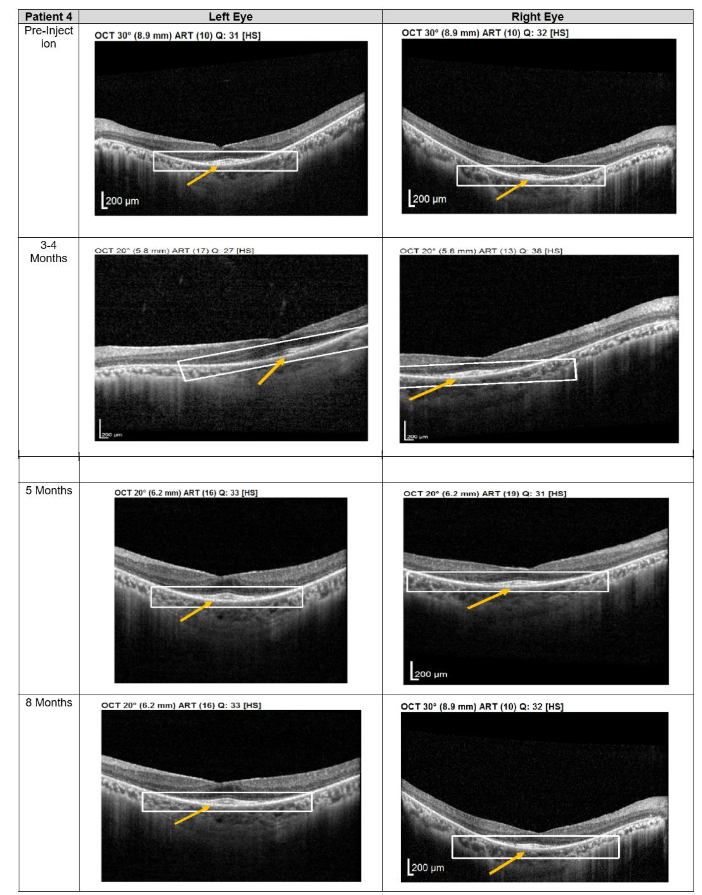

Patients 3 and 4

Patients 3 and 4 each received three subtenon MSC administrations at 4-6 weeks intervals, followed by follow-up visits every 3-4 months from December 2022 to November 2023. OCT imaging revealed a pronounced layer of photoreceptors accompanied by hyperreflective material at the interdigitation zone of the photoreceptor cells (PRCs), both at the macula and extramacular regions. These structural changes correlated with subjective reports from both patients of intermittent brighter vision, which persisted through the final follow-up.

Figure 4. Optical coherence tomography (OCT) images for both eyes of Patient 4 from pre-injection up to 1 year follow-up. Orange arrow demonstrates the presence of hyperreflective material at the interdigitation area of the photoreceptors at the macula and extramacular region. These were observed and maintained until the last follow-up examination.Discussion

At the 12-month follow-up, no adverse events were reported. As with the first two patients, no serious ophthalmic or systemic complications were observed, further supporting the safety profile of subtenon MSC administration.

Structural changes observed on optical coherence tomography (OCT) provide additional insight into the biological effects of treatment. All patients demonstrated persistent hyperreflective material localized at the interdigitation zone of the photoreceptors. Rather than representing fibrotic change, this OCT finding may reflect photoreceptor outer segment remodeling, improved mitochondrial activity, or enhanced metabolic integrity of surviving photoreceptors. Similar hyperreflective changes have been reported in studies evaluating MSC-mediated neuroprotection and are often associated with functional stabilization rather than disease progression. The stability of these OCT findings over extended follow-up in patients 1 and 2 suggests a sustained therapeutic effect rather than a transient inflammatory response.